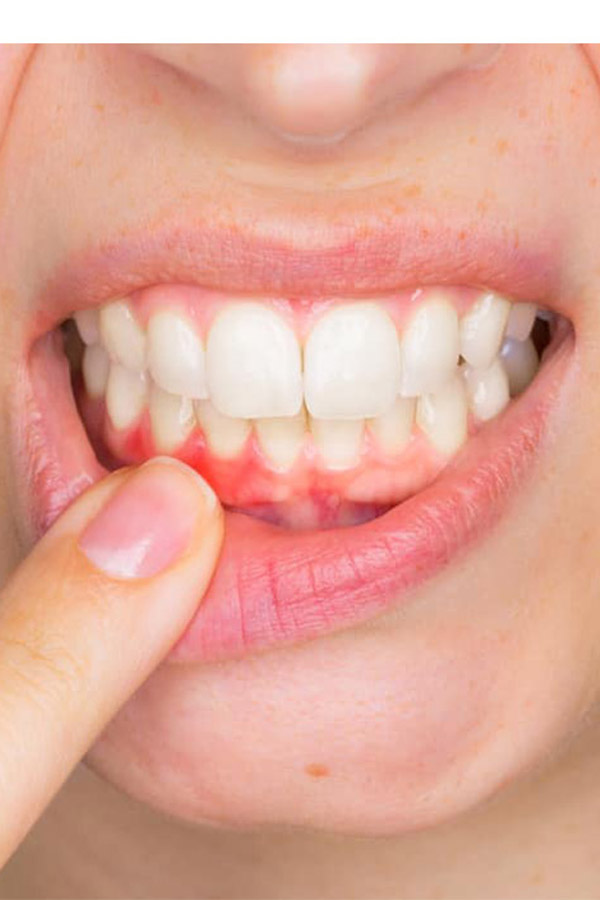

Parodontologia se ocupă de afecțiunile gingiilor și ale structurilor care susțin dintele, prin evaluare și tratamente adaptate stadiului bolii parodontale.

Profilaxia are rolul de a preveni apariția bolilor dentare, prin igienizări periodice și recomandări de îngrijire a dinților.